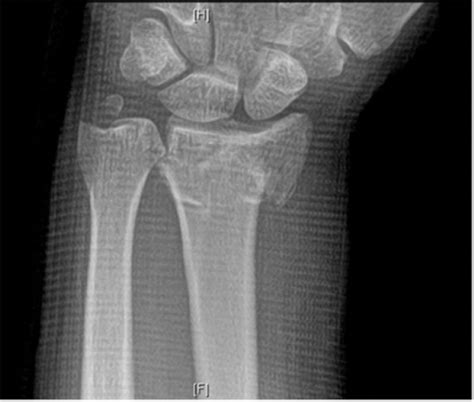

Distal radial fractures are a heterogeneous group of fractures that occur at the distal radius and are the these common fractures usually occur when significant force is applied to the distal radial. The fractures are not caused by radiation damage.

The distal radial fracture is the most common fracture of the forearm and accounts for approximately 16% of all skeletal fractures.